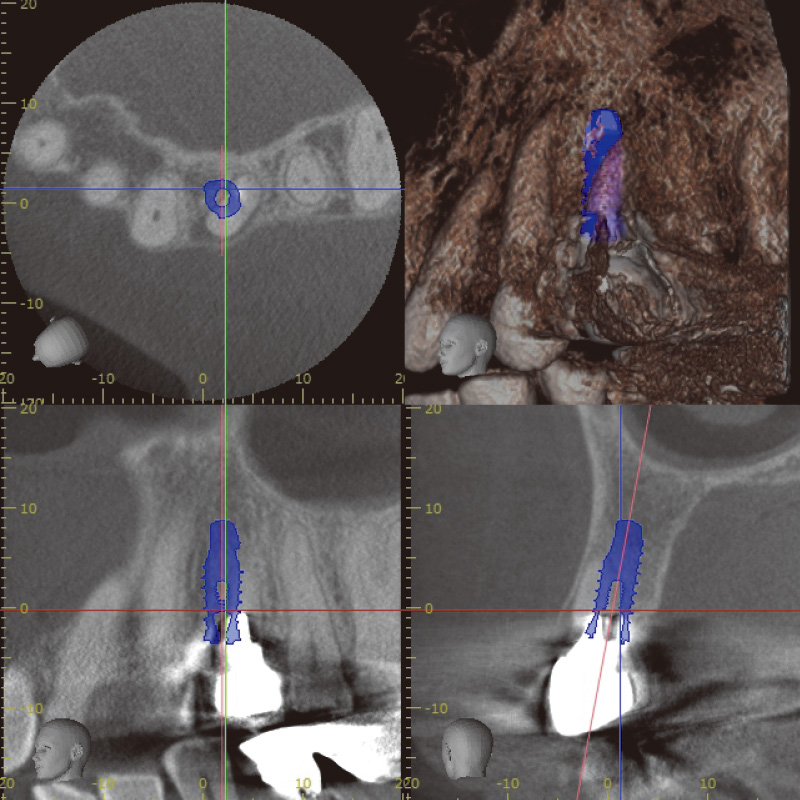

![[写真] 術前CT診断シミュレーション](/academic/dentalmagazine/wp-content/uploads/sites/2/2025/11/195-8_photo03.jpg)

図3 術前CT診断シミュレーション

1. 術前診断とインプラント埋入

術前診断には、CBCTを使用した。高精度な3D画像診断を行うことができ、骨質、骨量、根尖病巣、破折部位の状況を詳細に評価できるため、即時埋入に必要な治療計画を立てるのに非常に有効であった。特に、根尖部に疑われる破折線や歯根膜腔の拡大が確認され、SPIインプラントを選択し、即時埋入を実施した。